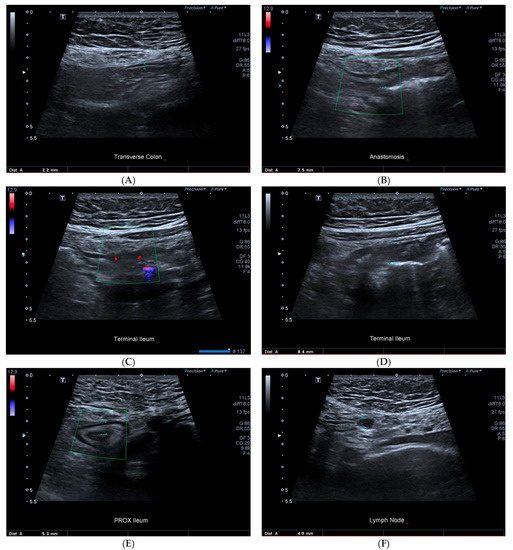

Contrast enhancement during IUS may further improve the identification of internal fistulae and abscesses in patients with CD. In a study of 67 patients with CD, the sensitivity of SICUS for detecting fistulae was 88% and 100% for identifying abscesses compared to surgical resection [41]. The concordance between SICUS and MRE was substantial for fistula detection (κ = 0.65) [41]. CEUS is particularly useful in differentiating between an abscess and an inflammatory mass. When performing CEUS, inflammatory masses show intralesional enhancement, while abscess enhancement is limited to the wall [21]. In a retrospective study of 71 patients with an intraabdominal mass, the differentiation between phlegmon and abscess with CEUS was comparable to cross-sectional imaging or surgical and percutaneous drainage (κ = 0.972) [18]. The overall sensitivity, specificity, and accuracy of CEUS for the diagnosis of abscess vs. phlegmon were 97%, 100%, and 98% [18]. In clinical scenarios whereby cross-sectional imaging is contraindicated, CEUS represents an attractive alternate to the detection and differentiation of intraabdominal masses related to CD. Illustrated examples of abnormal IUS parameters are shown in Figure 1.

Figure 1.

43-year-old female with prior ileocolonic resection with CD recurrence at the anastomosis and neoterminal ileum. (A) normal transverse colon, (B) anastomotic recurrence with increased bowel wall thickening, (C) terminal ileum showing Limberg three colour doppler signal, (D) terminal ileum wall thickening, (E) proximal small bowel wall thickening, (F) normal sized lymph node.